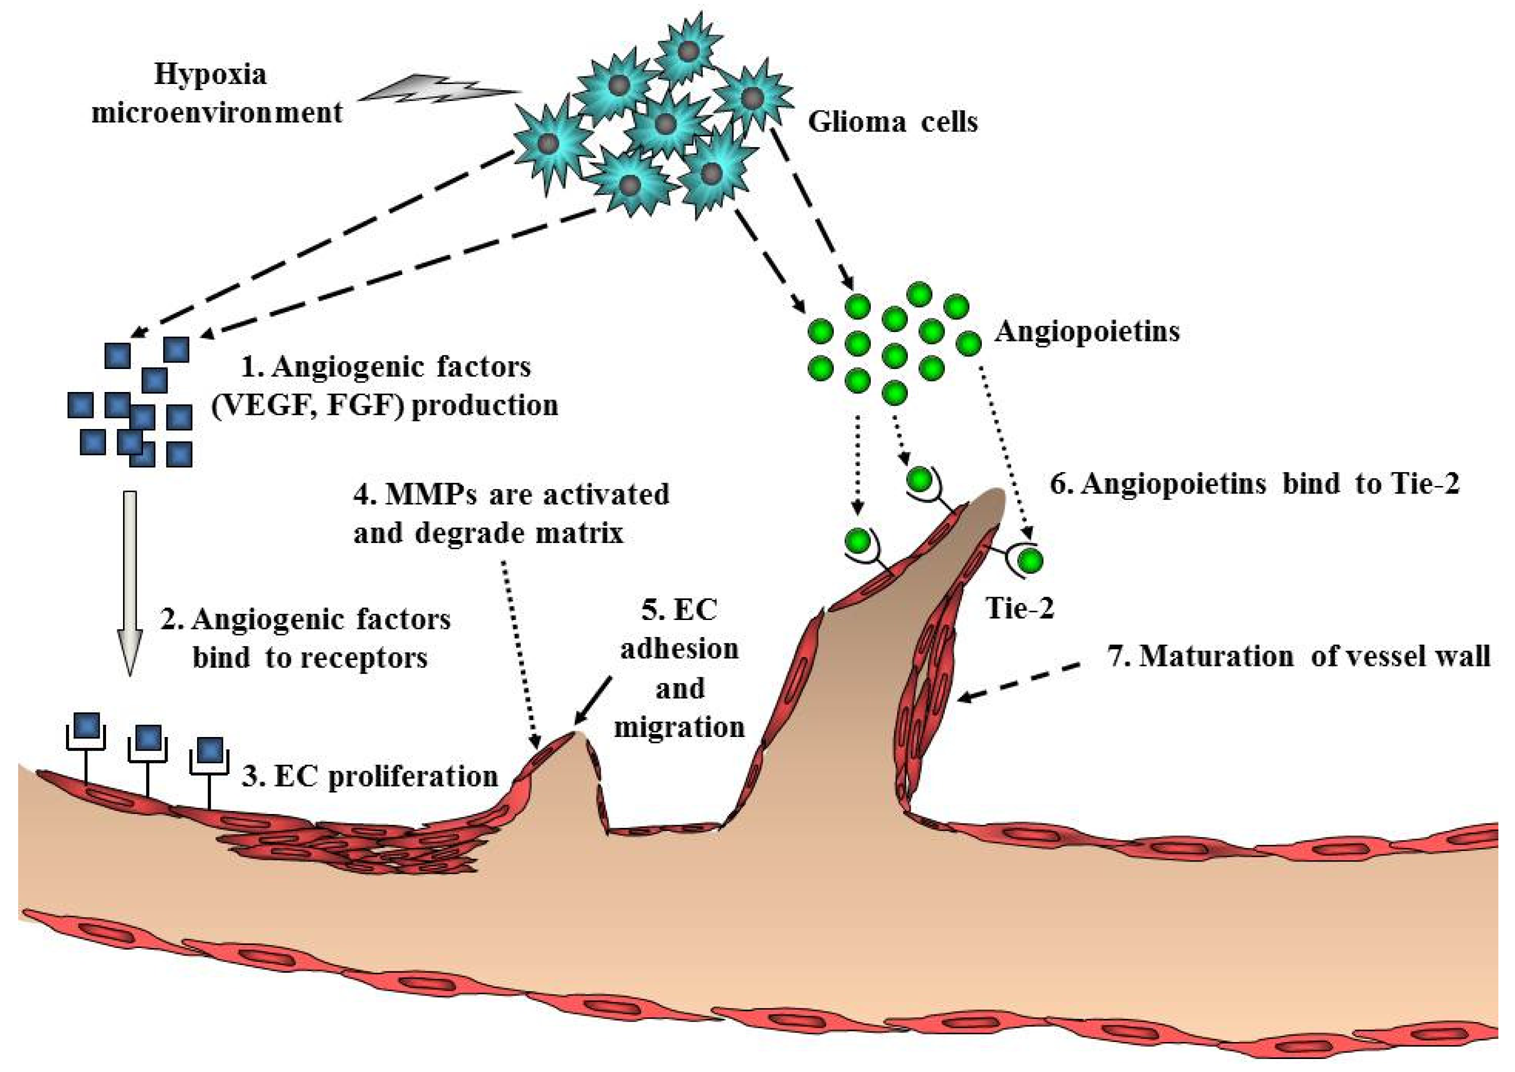

Ubiquitous angiogenesis is a hallmark of GBMs [53]. The degree of vascularization is significantly correlated with glioma malignancy, tumor aggressiveness, and clinical prognosis [54]. A number of scientists have aggressively investigated angiogenesis signaling and the function of angiogenic factors in malignant glioma. Many studies have implicated pro-angiogenic pathways including a sequence of coordinated events that is initiated by the expression of angiogenic factors such as VEGF with subsequent binding to its cognate receptors on endothelial cells (Figure 4). VEGF/VEGFR (VEGF receptor) participates in the formation of primitive blood vessels from progenitors, hemangioblasts/angioblasts, and the further development of blood vessels in glioma tissue [55,56]. Many other factors increase VEGF expression, including acidosis, nitric oxide, altered oncogenes, and tumor suppressor genes, cytokines such as bFGF, PDGF, and EGF, and activated intracellular signaling pathways such as PI3K/Akt and Ras/MAPK [57] (Table 1). Indeed, increased levels of VEGF and VEGFR in GBM have been reported [58,59].

Endothelial cell migration and proliferation are triggered by VEGF binding to its cognate receptors on endothelial cells [60]. Endothelial cells near the tumor strongly express VEGFR2, which establishes a paracrine signaling loop that stimulates the growth and proliferation of endothelial cells. Local degradation and breakdown of ECM occurs simultaneously, paving the way for newly sprouting vessels. Then, angiopoietins (Ang) are involved in the stability and maintenance of the tumor vasculature. Binding of Ang-2 to its cognate receptor, Tie-2, serves to destabilize vessels, which is a requirement for angiogenesis of glioma [2] (Figure 4). Another key angiogenic process involves cathepsin B and matrix metalloproteinases (MMPs), as well as the expression of matrix proteins such as fibronectin, laminin, tenascin-C, and vitronectin [61]. Formation of the new blood vessel is accomplished by endothelial cells that form a lumen. Individual sprouts are then connected to form vascular loops, through which blood begins to flow. Maturation of the vessel wall then begins by recruitment of pericytes to assemble along the endothelial cells outside the new vessel. The angiogenic process of glioma is completed by the formation of a new basement membrane [62].